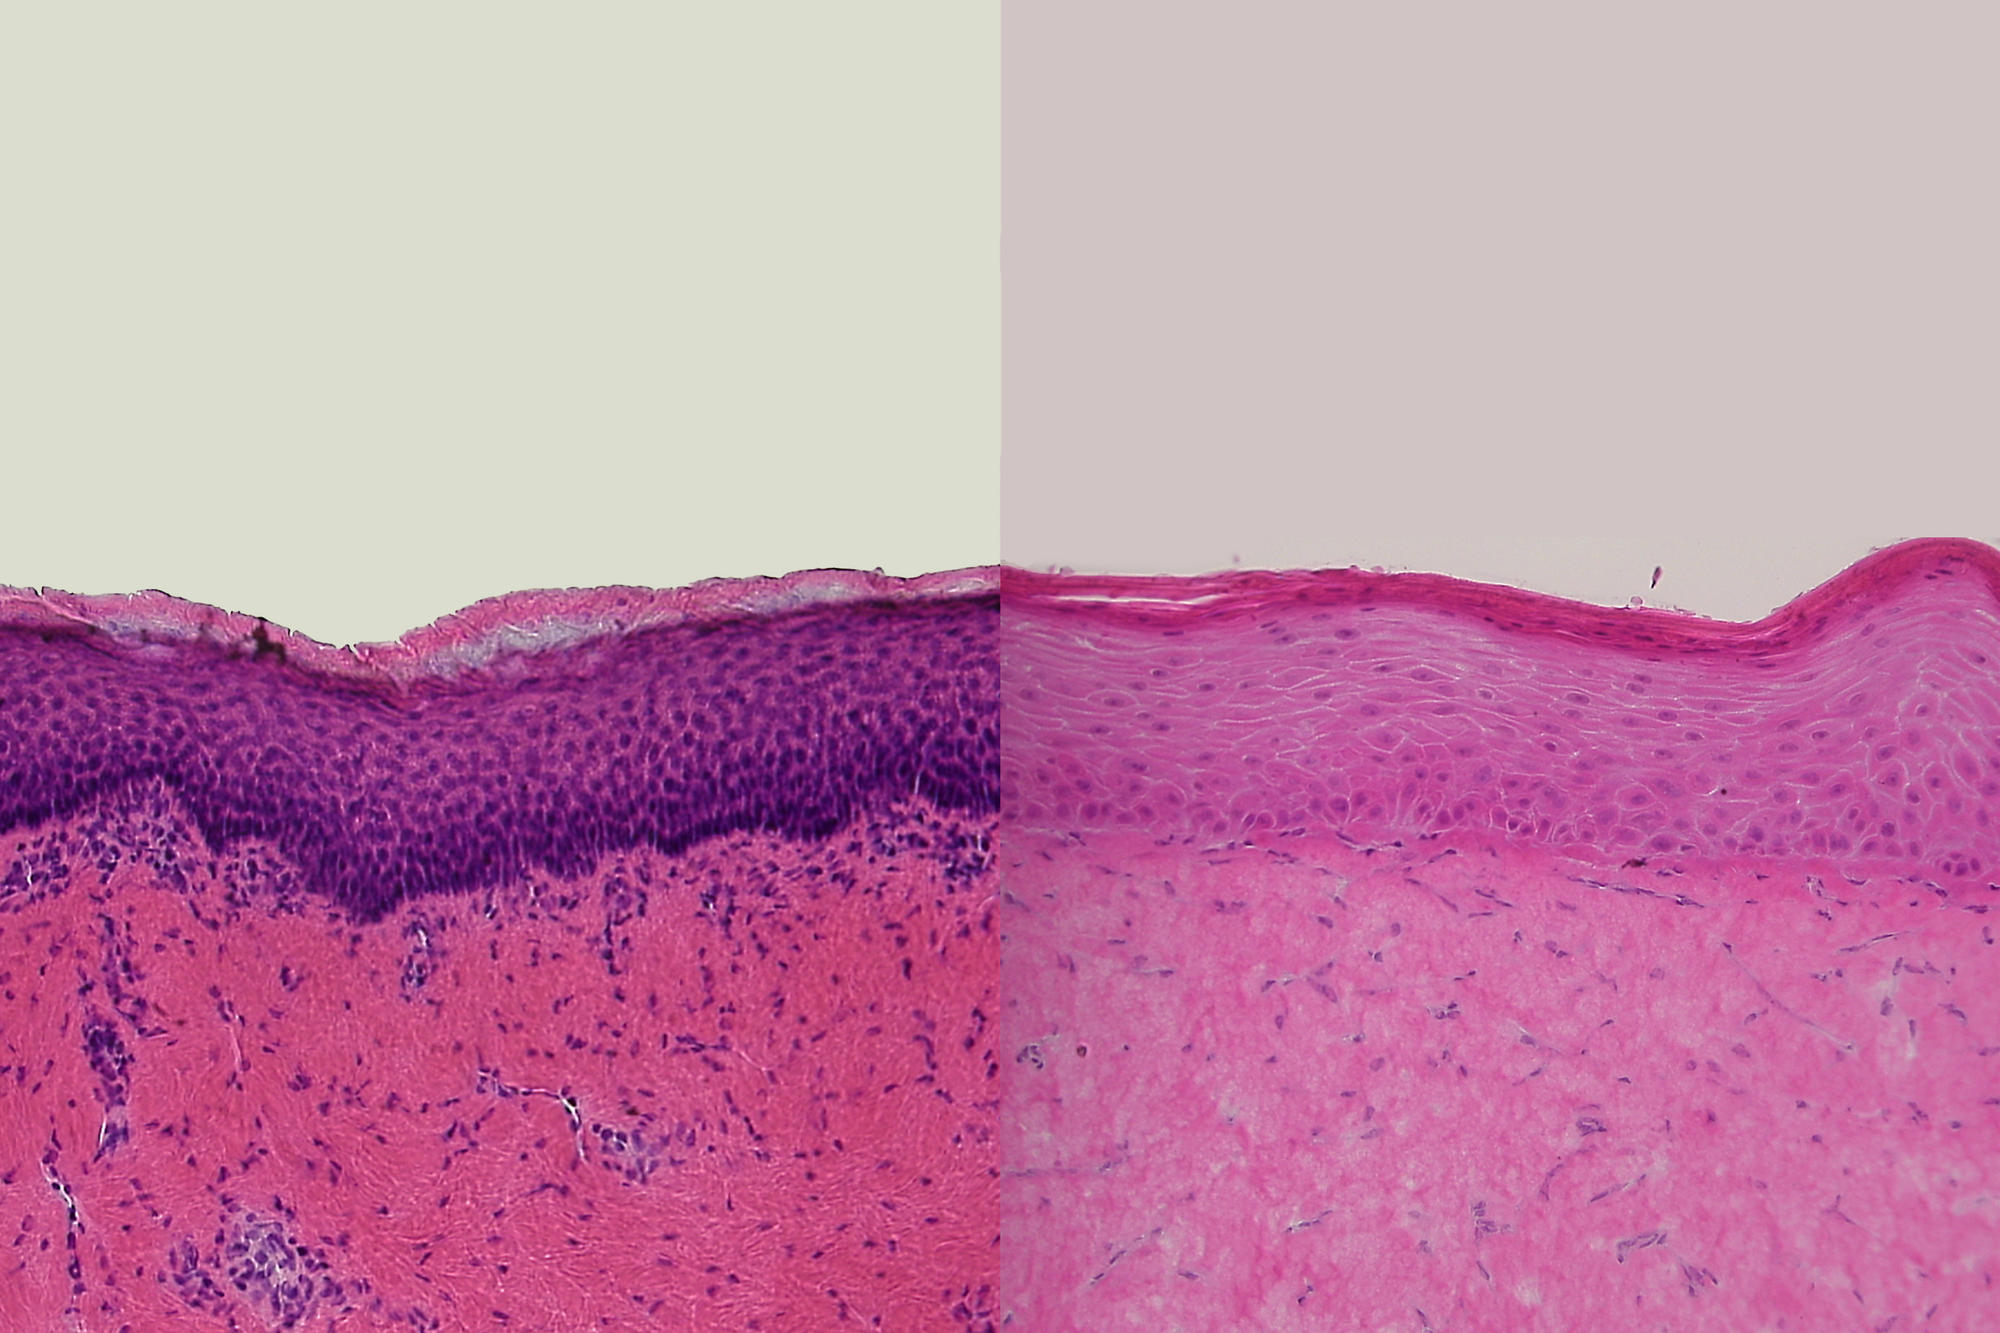

Die Querschnitte durch Humanhaut ex vivo (links) und durch rekonstruierte Humanhaut (rechts) zeigen große Ähnlichkeiten und sind Ausgangspunkt für die Nutzung von rekonstruierter Humanhaut in der Erforschung von Hautkrankheiten.

Bildquelle: Christian Hausmann